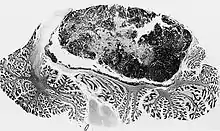

Нейроонкология возникла и развивалась одновременно с нейрохирургией. Первая нейрохирургическая операция была проведена в Глазго в 1879 году шотландским хирургом Вильямом Макэвеном (W. Maceven), в ходе которой с благоприятным исходом была удалена менингиома у женщины.[1][2] Первая успешная операция по удалению опухоли головного мозга была проведена в Риме Ф. Дюрантом (F. Durante) в 1884 году.[1] В 1887 году Виктор Горслей впервые успешно удалил интрадуральную спинальную опухоль, находящуюся на уровне IV грудного сегмента.[1]